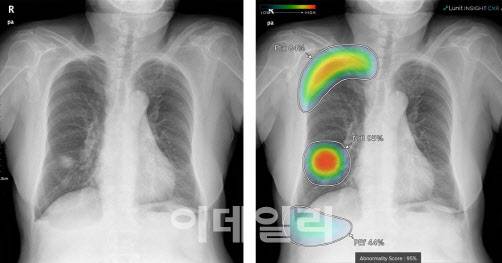

[이데일리 김승권 기자] 루닛(328130)이 생성형AI 모델 개발이 막바지 단계인 것으로 파악됐다. 카카오에 이어 의사들의 판독을 돕는 방식의 생성형AI 출격을 예고한 것이다.

일단 1차적으로 흉부 엑스선 이미지에 대해 구조화된 텍스트 판독문을 생성하는 모델을 내놓을 것으로 예상된다. 이어 유방촬영영상 분석 모델 등으로 확장할 예정이다.

25일 AI의료업계에 따르면 루닛은 최근 영상을 판독하고 의사들이 볼 수 있는 간단한 판독문을 작성해 줄 수 있는 흉부X선 관련 생성형AI 모델 시연을 마쳤다. 상용화 시기는 알려지지 않았지만 데이터 학습을 지속적으로 진행 중인 과정으로 파악된다. 챗GPT, 구글 등 해외 업체와 한국의 카카오브레인에 이어 의료 분야 생성형AI 탄생을 예고한 것이다.

루닛에 따르면 해당 AI는 현존하는 가장 최신의 메디컬 LLM들을 뛰어넘는 성능을 구현할 수 있게 만들어지고 있다. 기존 루닛 인사이트 제품이 가지고 있던, 제한된 개수의 병변 만을 검출하는 한계를 뛰어넘는 제품이 될 예정이라는 것이다.

백승욱 루닛 의장 또한 해당 모델에 대한 기대감은 나타낸 바 있다. 백 의장은 한 인터뷰에서 “예전 모델은 엑스레이를 집어넣으면 여기 어떤 질환이 있는지 우리가 지원하는 10개의 병변에서만 결과를 내놨다”며 “하지만 생성형AI 모델은 모든 판독문과 모든 영상을 가지고 학습을 한 거기 때문에 모든 질병 가능성을 이야기해 줄 수 있다”고 설명했다.